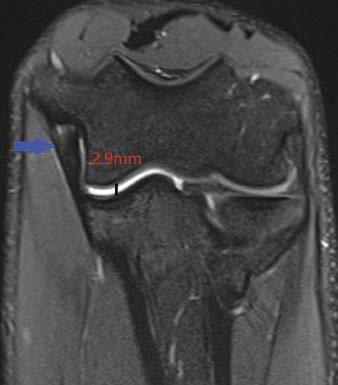

A total of 44 MLB pitchers underwent elbow MRI, including both standard sequences and a coronal fat-saturated proton density-weighted sequence in the FEVER view using specific positioning maneuvers and sandbags to immobilize the elbow in valgus stress, while visualizing the UCL parallel to its long axis. To measure UT joint space and assess confidence in UCL-related findings with overall UCL normality, two radiologists independently evaluated standard and FEVER views.

"Among 44 MLB pitchers undergoing elbow MRI," Knoblauch et al. continued, "the FEVER view, compared with standard view, yielded increased UT joint space width (mean increase, 1.80 mm) and increased confidence for three of five UCL-related findings (mean increase, -0.14 to 0.98)." Readers 1 and 2 classified 3 and 2 additional UCLs as abnormal on FEVER compared with standard view; neither reader classified any UCL as abnormal in standard view but normal in FEVER view.